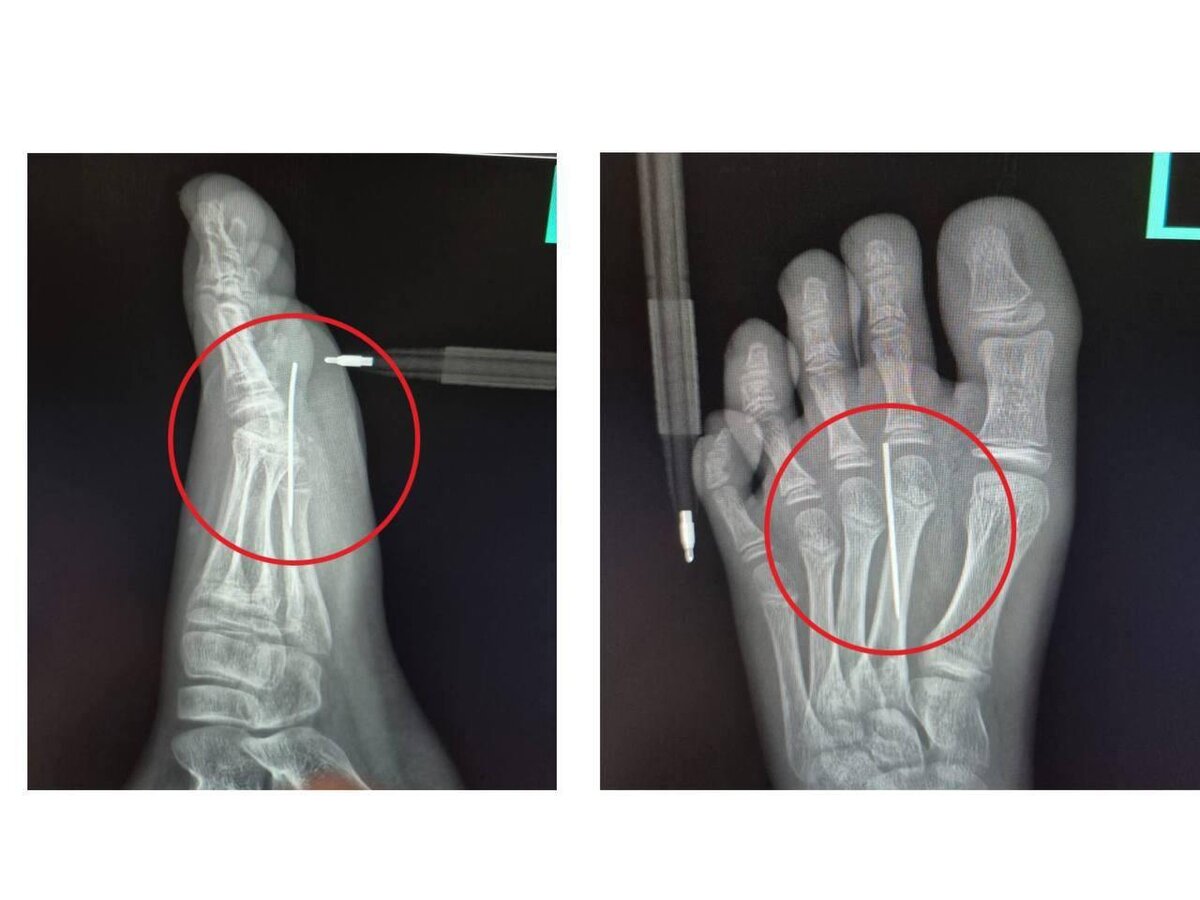

10-летний мальчик наступил на иглу и попал в больницу из-за «Игры в кальмара». Ребенок повторял дома в Подмосковье задание с печенькой, в котором нужно было вырезать фигурку с помощью иглы. Однако во время игры мальчик наступил на одну из них, и она проткнула ногу. Парня пришлось везти в больницу, где иголку аккуратно извлекли в течение трех минут. Сейчас его здоровью ничего не угрожает. ⭕ Подписаться | Прислать новость | Буст

10-летний мальчик наступил на иглу и попал в больницу из-за «Игры в кальмара».

Ребенок повторял дома в Подмосковье задание с печенькой, в котором нужно было вырезать фигурку с помощью иглы. Однако во время игры мальчик наступил на одну из них, и она проткнула ногу.

Парня пришлось везти в больницу, где иголку аккуратно извлекли в течение трех минут. Сейчас его здоровью ничего не угрожает.